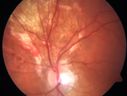

AVM1053 viewsFP of AVM in OS of a 48 yr old female.Mar 11, 2014